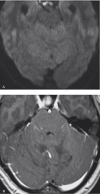

Lhermitte-Duclos disease is a rare pathologic condition consisting of a dysplastic gangliocytoma of the cerebellum. Its association with phacomatosis and an autosomal dominant neoplastic syndrome, Cowden's syndrome is also known. Modern neuroimaging contributes to a correct diagnosis and pre- and postoperative evaluation. Here we describe the morphologic and metabolic aspects of the disease as shown by conventional MRI, diffusion imaging and spectroscopy in a 31-year-old woman. In addition, the specific neuroradiologic characteristics are presented and discussed in the light of the main pathologic and clinical features, such as hypertrophy of the cerebellar folia associated with white matter atrophy.